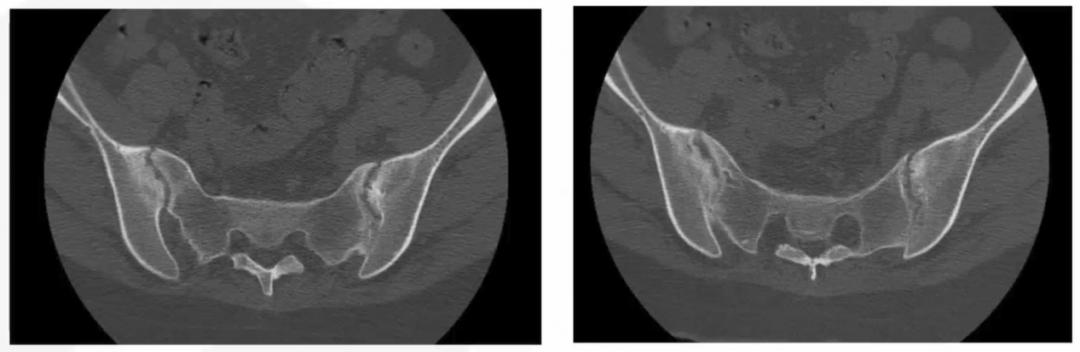

图1 患者X线正侧位图

图2 患者骶髂关节CT胸部CT:双肺陈旧病变,脾大;

骶髂关节CT:符合AS改变,建议结合临床;

腰椎X线:未见异常;

确实,如前文所见,患者的诊断十分清晰:青年女性,病史10年,近期加重,临床表现为多关节疼痛,累及中轴及外周关节,呈炎性腰背痛特点,检查HLA-B27阳性,骶髂关节X线、CT提示骶髂关节炎改变,根据1984年修订的纽约标准,可诊断为AS。